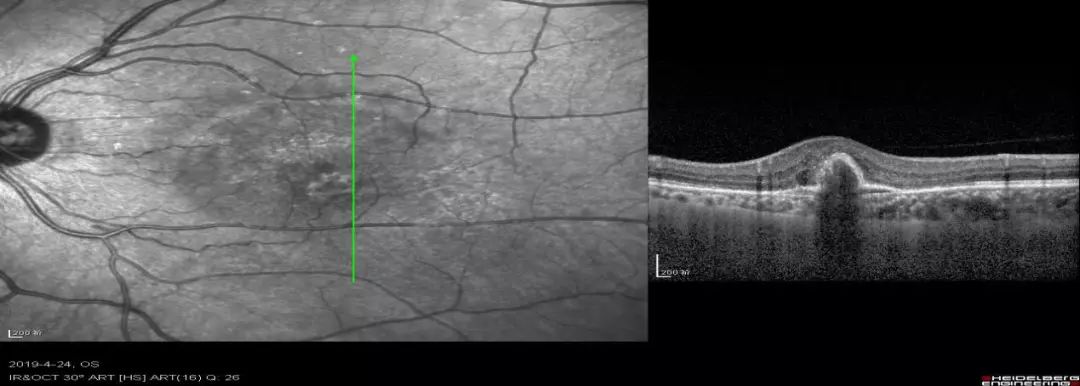

急性特发性黄斑病变一例

图片尺寸1634x797